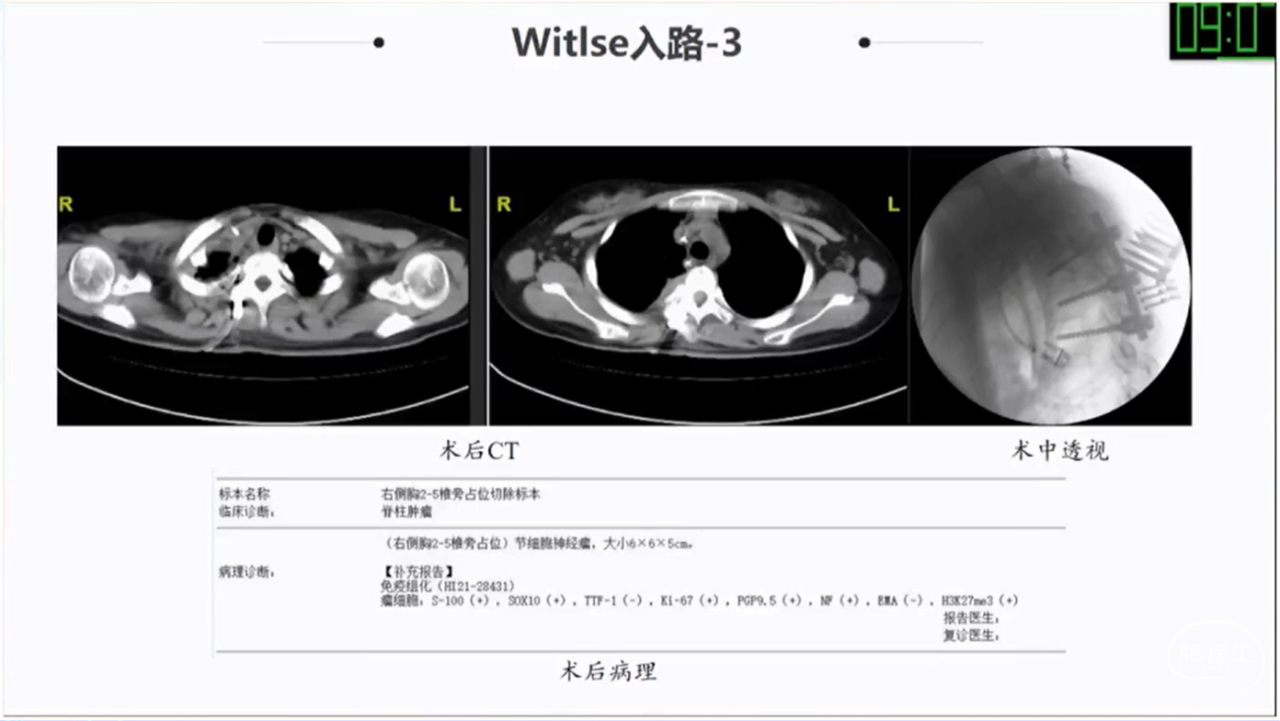

· Witlse入路治疗椎旁巨大肿瘤优势明显